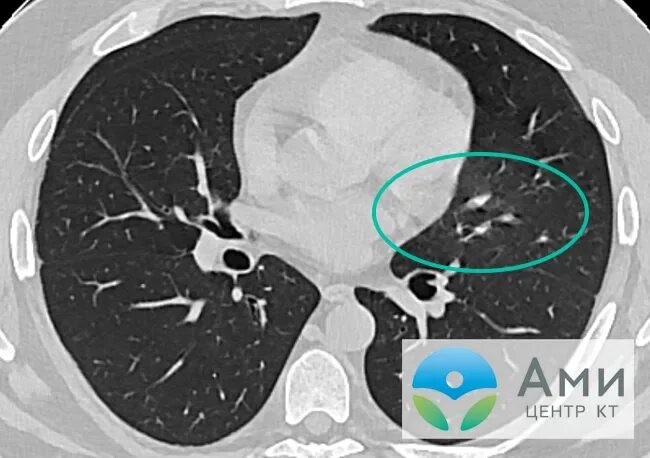

Фиброз кт